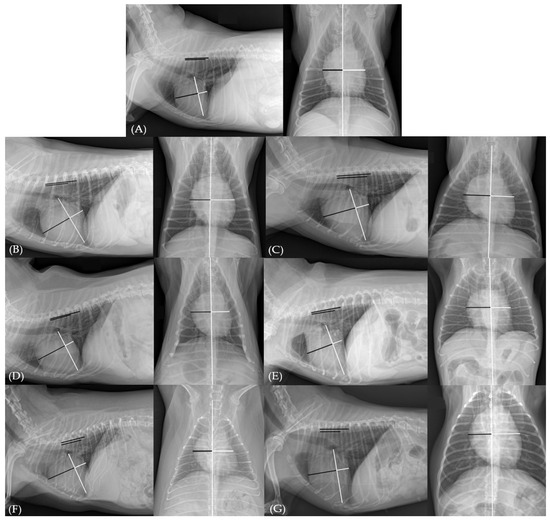

Breed-Specific Variations in Vertebral Right Heart Index (VRHi): Implications for Detection of True and False Right Heart Enlargement (RHE) in Dogs

by Kawon Choi, Jaehwan Kim, Kidong Eom, Jongwon Koo, Inseong Jeong and Chul Park

Vet. Sci. 2025, 12(4), 300; https://doi.org/10.3390/vetsci12040300 - 24 Mar 2025

This study investigated breed-specific variations in vertebral right heart index (VRHi) values and their diagnostic accuracy in detecting right heart enlargement (RHE) in dogs. A total of 359 dogs from various breeds, including brachycephalic and non-brachycephalic groups, were evaluated using radiographic and echocardiographic [...] Read more.

This study investigated breed-specific variations in vertebral right heart index (VRHi) values and their diagnostic accuracy in detecting right heart enlargement (RHE) in dogs. A total of 359 dogs from various breeds, including brachycephalic and non-brachycephalic groups, were evaluated using radiographic and echocardiographic methods. The VRHi was measured from lateral (RL) and ventrodorsal (VD) thoracic radiographs. Certain breeds, such as brachycephalic dogs, Schnauzers, Dachshunds, Pomeranians, Yorkshire Terriers, and Miniature Pinschers, demonstrated significantly higher VRHi values than non-brachycephalic breeds, even without true RHE. The RL VRHi showed stronger clinical relevance than the VD VRHi, correlating better with the echocardiographic findings. Breed-specific diagnostic cutoff values were established: RL VRHi ≥ 3.45 vertebral units (v) (sensitivity: 75%, specificity: 75%) and VD VRHi ≥ 2.75 v (sensitivity: 72%, specificity: 72%) for brachycephalic breeds and RL VRHi ≥ 3.25 v (sensitivity: 78%, specificity: 80%), VD VRHi ≥ 2.4 v (sensitivity: 61%, specificity: 61%) for non-brachycephalic breeds not belonging to the aforementioned categories. Body weight and chest conformation showed no significant association with VRHi values. These findings highlight the necessity of considering breed-specific factors in radiographic cardiac evaluations, as some breeds may present radiographic signs of RHE despite a normal cardiac anatomy and function. Full article

Figure 1